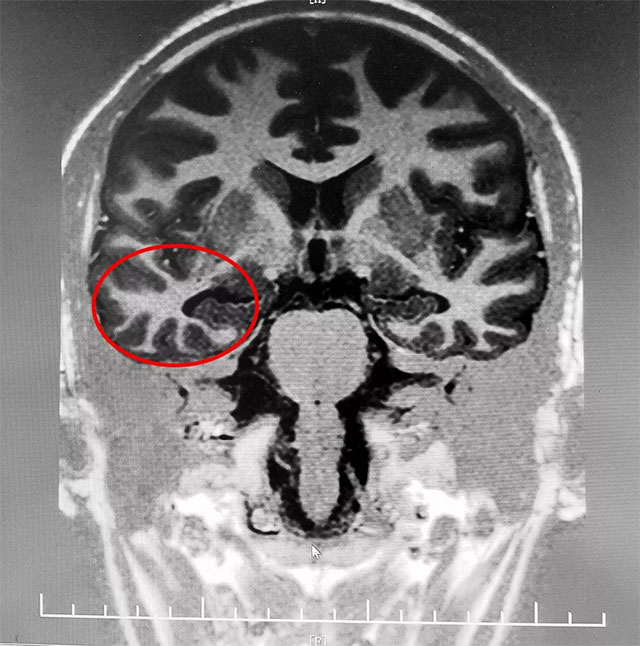

經(jīng)檢查,患者臨床主要表現(xiàn)為復(fù)雜部分性發(fā)作繼發(fā)全面性發(fā)作。腦電監(jiān)測期間發(fā)作兩次,24H長程視頻腦電監(jiān)測有明顯異常波。MRS海馬示:代謝異常,海馬硬化。

綜合各項(xiàng)檢查最終明確治癲灶位于右側(cè)額葉、右側(cè)顳葉、右側(cè)海馬;颊呓(jīng)長期系統(tǒng)內(nèi)科藥物治療不佳,確診為難治性癲癇,并且經(jīng)過系列檢查可明確病變位置。經(jīng)過系統(tǒng)全面評估,手術(shù)指征明確,未見明顯手術(shù)禁忌。